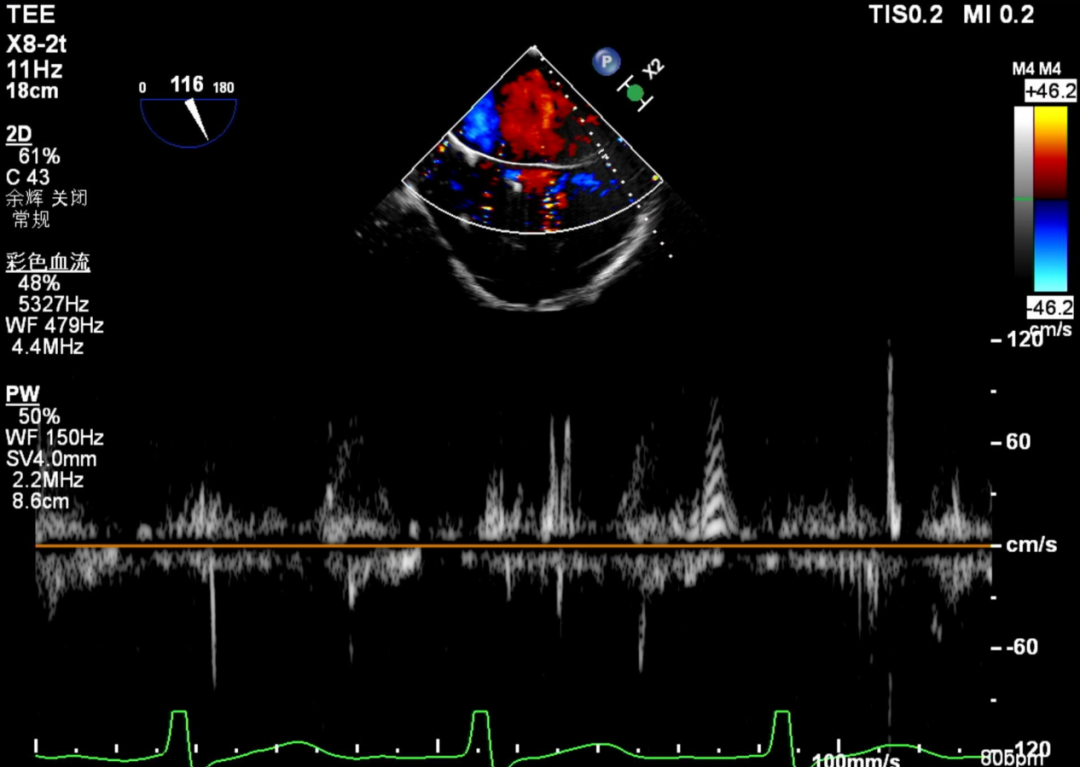

术前TEE评估

术前瓣膜介入团队的心超医生陈星星医师王良国医师对患者的心脏结构和瓣膜解剖情况进行详细的评估:

1.二尖瓣重度关闭不全(4+),瓣环明显扩大(AP径4.6cm,LM径3.9cm),扁平,关闭时瓣叶对合不佳(carpentier I),1-3区均可见反流束,返流宽度达26mm;肺静脉频谱呈收缩期反向。

术前肺静脉频谱